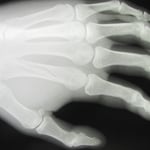

●右第3中手骨骨折

中学2年生 ラクビープレー中に骨折をしました。

当初、整形外科の診察を受けギプス固定をしてもらいましたが、

ボクシンググローブのような大きなもので、しかもギプスが皮膚を圧迫していたので当院に相談されました。

3週間後には大事な試合が待っています。

提携の整形外科で再度レントゲン検査をしてもらい転移(骨のずれ)がないことを確認し小さな固定にかえました。

毎日来院してもらい超音波治療とマッサージをしました。

2週経過した頃から圧痛(折れたところを押したときの痛み)は消失し、なんとか試合に間に合いました。

念のためさらに1週間来院してもらい治療を終了しました。